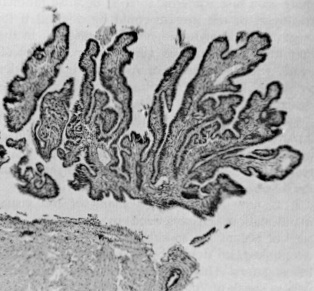

La présence d’autres tissus mülleriens ectopiques, tels que les tissus cervicaux, myométriaux et tubaires (Figure 1) [31], signifie simplement que tout composant cellulaire müllerien risque de se différencier ou de migrer de façon aberrante. Parmi eux, le futur tissu endométrial est de loin le plus courant et le plus symptomatique.

Les différents degrés de différenciation histologique qui se produisent au niveau intralésionnel et interlésionnel (figures 2 et 3) peuvent résulter d’une maturation incomplète au cours de l’embryogenèse ou alors des niveaux variables et faibles de récepteurs aux œstrogènes et à la progestérone présents dans les lésions [32, 33, 34] ; cette variabilité et cette faiblesse peuvent elles-mêmes être le résultat d’une maturation incomplète. Lorsqu’un diagnostic pathologique de « reste glandulaire mésothélial » est posé, il renvoie soit à une glande endométriale qui a été sectionnée sans le stroma, soit à une forme fruste d’endométriose.